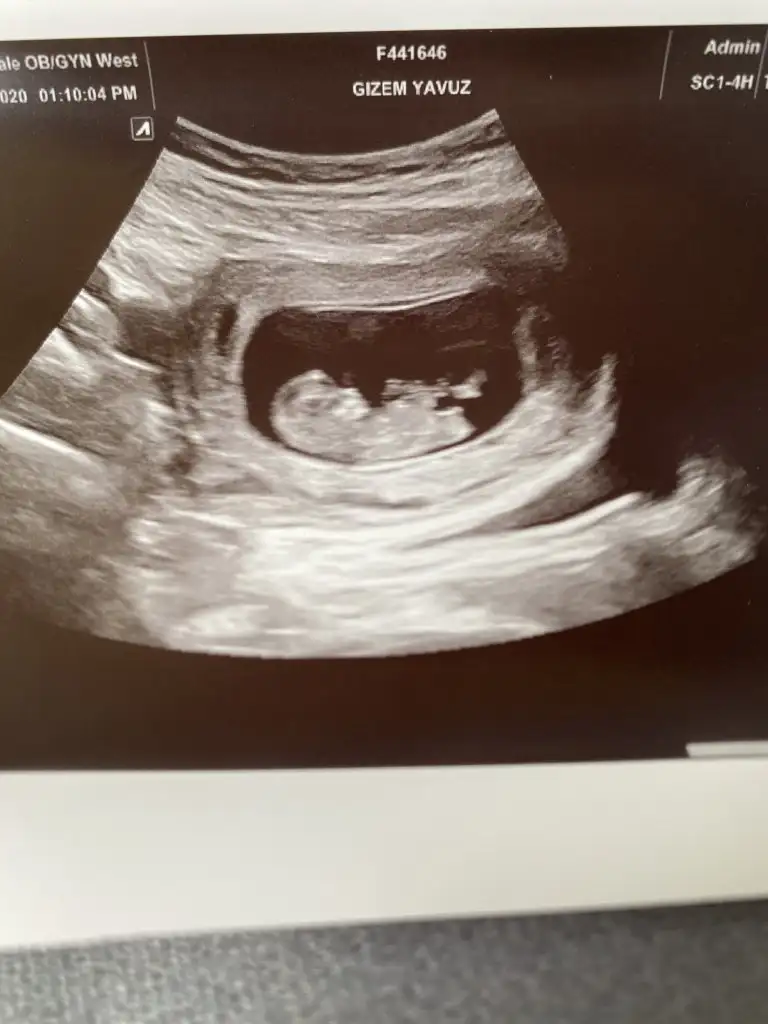

masallah canım kac haftalıkKızlar az önce doktordan geldim bir bakın bakalım cinsiyet tahmini yapabilecek misiniz Remzi teorisine göreÇin takviminde bakmayı beceremedim

MaşAllah MaşAllah MaşAllah ben erkeğe benzettim teorili bakmadım ama he anlamam o işlerden sadece içimden öle geldi sağlıkla doğsun inşAllahKızlar az önce doktordan geldim bir bakın bakalım cinsiyet tahmini yapabilecek misiniz Remzi teorisine göreÇin takviminde bakmayı beceremedim